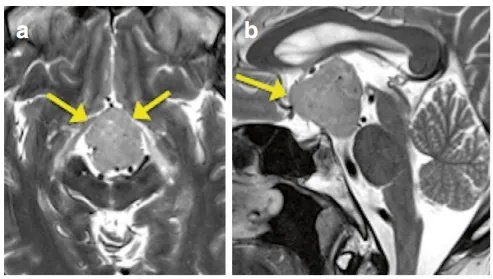

但是醫(yī)生讓我做頭部檢查,直到我做了MRI檢查,答案才殘酷地?cái)[在面前:我的腦子里長(zhǎng)了一個(gè)腫瘤。醫(yī)生指著MRI圖像(圖a、b)告訴我,這個(gè)鞍上腫瘤已經(jīng)壓迫到了關(guān)鍵的大腦區(qū)域——向腳間池延伸并致中腦大腦腳受壓變形。

影像